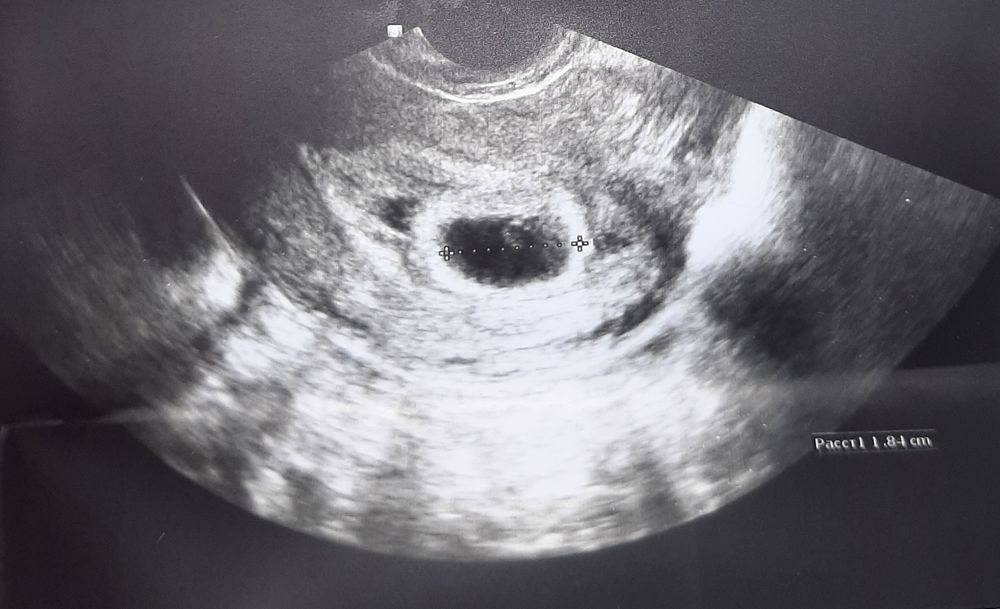

Пустое плодное яйцо?

Я тоже примерно на таком сроке делала. Эмбрион ещё не визуализировался. Но УЗИ было экспертного уровня, как будто картинка была более четкая и Ре сказала, что есть эмбрион, но прям крошка, даже ктр не замерить. А на 6 неделе уже появился - 4,5 мм.

Ровно в 5 недель ПЯ было 5мм и там ничего не видно было конечно. В 7 недель все было хорошо и сердечко и тд. Постарайтесь не переживать сильно и раньше времени.

У меня в 5.2 было только ПЯ, но размерами гораздо меньше, 6 мм было

У меня на 5нед ПЯ 9мм ЖМ 2.7мм